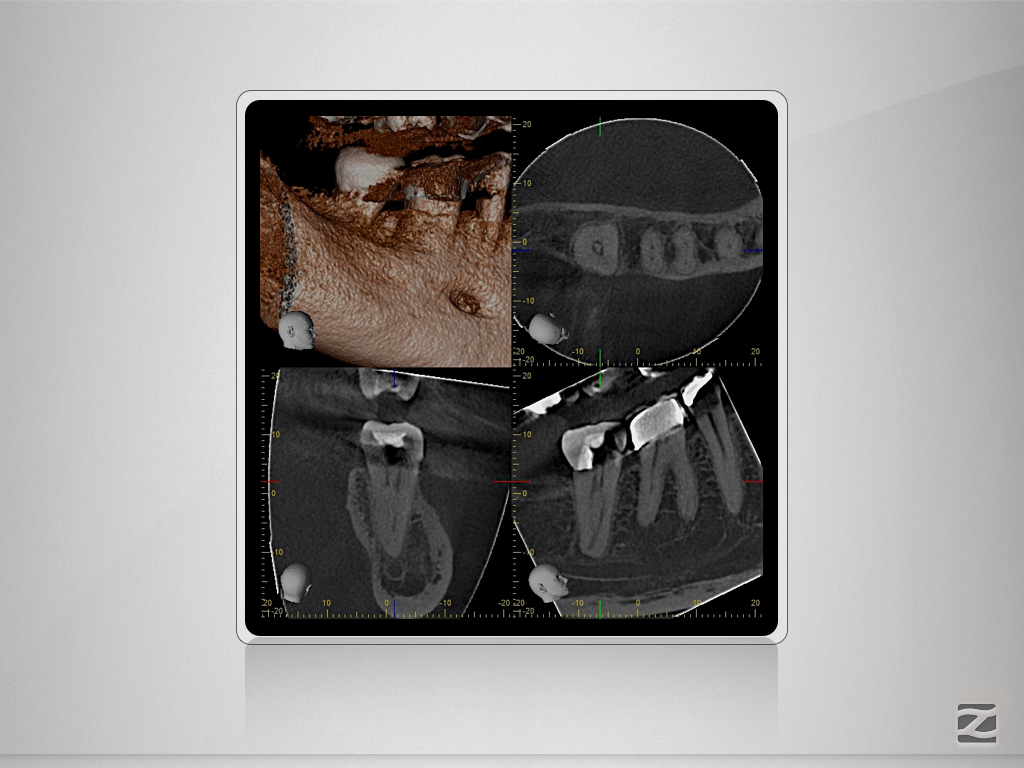

47d-002

„C“ ja – „C“ nein